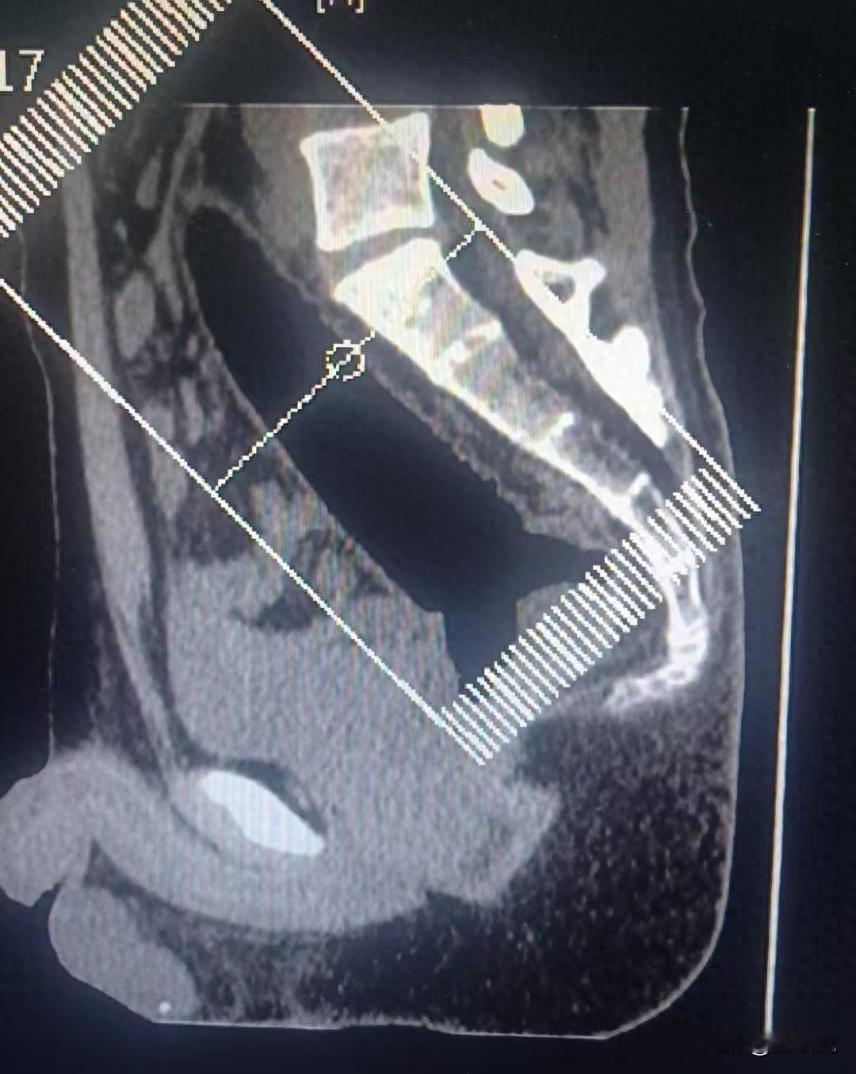

太离谱了!河南郑州,一男子捂着屁股去医院肛肠科看病,可问诊时,男子却扭扭捏捏说屁股卡了一个东西,开始医生还以为问题不大,可看了才发现,这哪是卡了东西,一根异物已深入直肠,最后手术后取出一根22厘米异物。网友:这是个狠人 医生介绍,该男子今年26岁,捂着屁股、夹着腿走进肛肠科的。人一坐下,表情写满不舒服,可嘴上偏偏说得含糊,只反复提一句屁股里卡了个东西 接诊的医生起初并未太过意外,肛肠科偶尔会遇到类似病例,通常是小物件,处理起来不算复杂。但当他开始检查时,情况却远超预期 异物已经完全进入直肠,外面根本看不见,指诊能摸到,却判断不了具体形状。拍了片子,影像也不清楚,只能看到一团模糊的影子。追问之后才知道,是硅胶材质的物件,透明、不显影,这才把情况说通了 医院立即安排紧急手术。在腰麻下,医生借助专业器械,在直肠内小心翼翼地操作。当异物终于被完整取出时,在场医护都感到震惊——那是一根长达22厘米、直径3.2厘米的硅胶棒 说起来,这类病例在肛肠科并不算罕见,只是多数人避而不谈。医生表示,他们接诊过的直肠异物五花八门,有日常生活用品,也有刻意放入的物品。每次遇到,医护人员的首要任务都是解除健康威胁,而非评判患者 这件事让人尴尬,也很现实。身体不是试验场,很多所谓的小刺激、小尝试,一旦越界,后果就只能自己扛。出了问题早点去医院,不是示弱,是对自己负责。真等到忍不了再来,受罪的时间更长,风险也更高